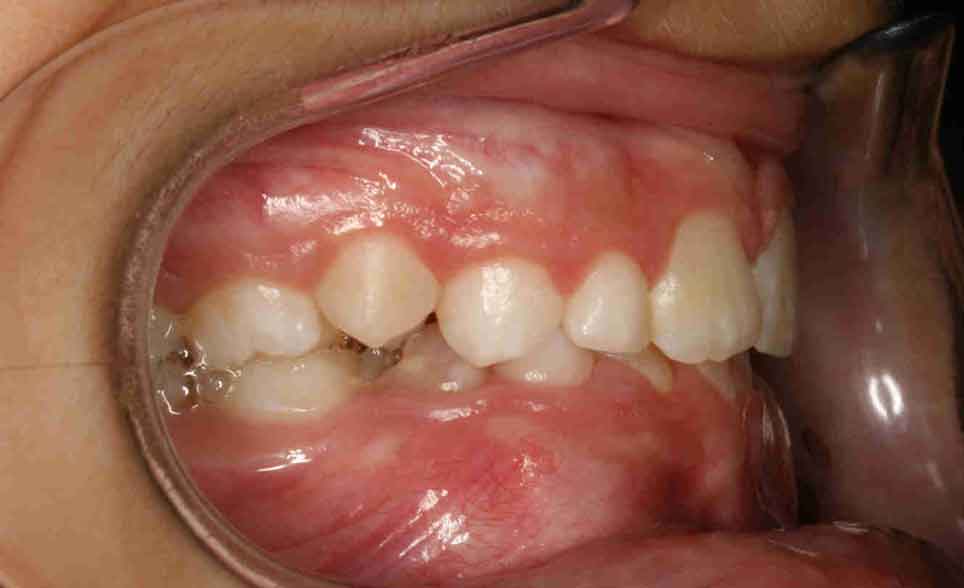

Ondorengo irudietan tratamenduaren emaitza desberdinak ikus daitezke, erdiko barra alde batetik bestera irristatuz.